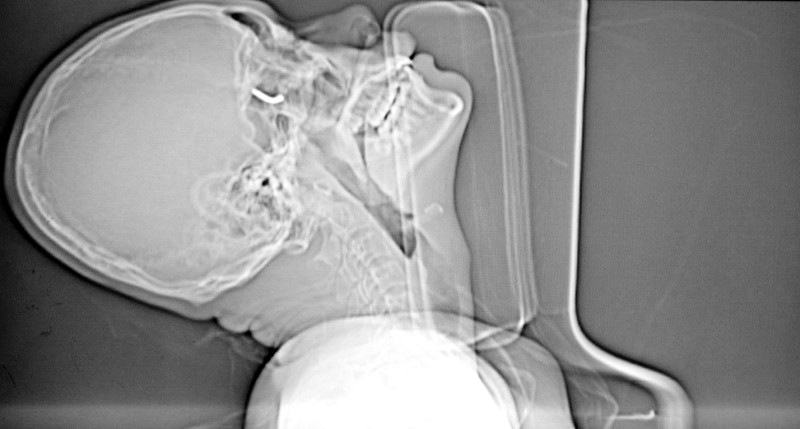

台海网9月3日讯 (海峡导报记者 李立宇 见习记者 沈华铃/文 张向阳/图)8月30日下午两点多,在海沧一处楼盘内,一名工人用射钉枪安装铝合金门窗,不料射出的射钉竟反弹回来,击穿鼻孔,射进右侧眼眶,险些失明。

2日上午,记者在中山医院见到了这名20岁的林姓工人,击中他的射钉已被取出,他正在病床上休息,从外表看不出伤痕,但耳鼻喉科副主任医师杨海斌告诉记者,那射钉如果再刺入半毫米,他可能就永远失明了。

随后,记者在杨医生的办公室那看到了那枚“惹祸”的射钉,长约3厘米,直径约2.5毫米。当时,射钉击中墙壁后反弹回来,从林某左侧鼻孔穿入,先后击穿鼻中隔和鼻窦,最后击中了右侧眶尖,林某眼前顿时一片黑暗,过了五六分钟,他的视力才慢慢恢复。“这是视神经受到强烈冲击造成的。”杨医生指着CT片说,射钉已经紧紧贴在林某的视神经上,使视神经受到压迫,只差一毫米就会将视神经打断,那样工人将会失明。